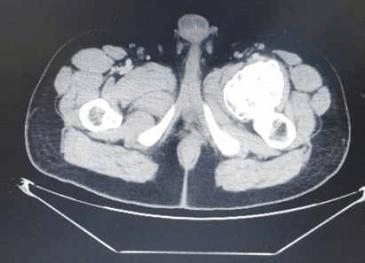

এখানে আমরা প্রক্সিমাল ফেমোরাল অস্টিওকন্ড্রোমার কারণে বাম নিতম্ব এবং উরুতে ব্যথা সহ একজন 28 বছর বয়সী পুরুষ উপস্থিত প্রতিবেদন করি। রেডিওগ্রাফ দেখায় ফুলকপির মতো ভর বাম প্রক্সিমাল ফিমার থেকে উদ্ভূত। বাম উরুর 3D CT স্ক্যান বিভাজনের কাছাকাছি ফেমোরাল জাহাজের সংকোচন পূর্ববর্তী স্থানচ্যুতি দেখায়। এই রোগীকে অস্ত্রোপচারের এন-ব্লক রিসেকশনের মাধ্যমে চিকিত্সা করা হয়েছিল এবং হিস্টোপ্যাথলজি অস্টিওকন্ড্রোমার ডায়াগনস্টিক ছিল।

অস্টিওকন্ড্রোমা বাম ফিমারের সাবট্রোচ্যান্টেরিক অঞ্চলের অ্যান্টেরো-মিডিয়াল দিকের উৎপত্তি যেখানে একটি বৃহৎ কার্টিলাজিনাস ক্যাপ সহ কম ট্রোক্যান্টারকে বিচ্ছিন্ন করে বিভাজনের কাছাকাছি ফেমোরাল জাহাজের সংকোচন পূর্ববর্তী স্থানচ্যুতি ঘটায়।

3D সিটি স্ক্যান